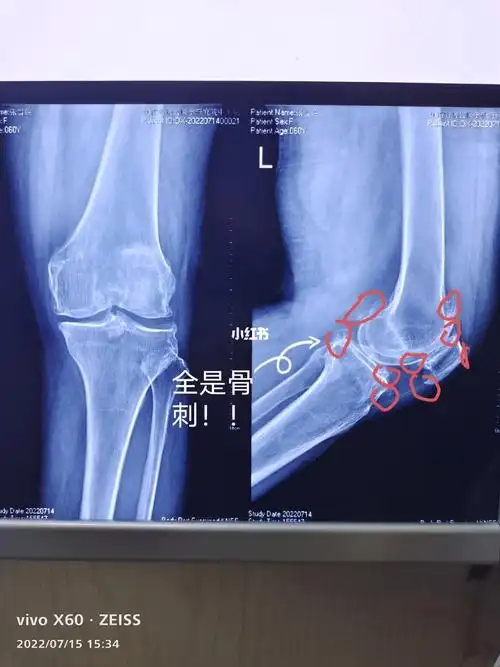

老年人膝盖骨刺怎么办怎么治疗呢

膝关节疼痛难忍,长"骨刺"了该怎么办?

问:请问我这膝盖骨头长刺的情况严重么?

膝关节骨刺处理